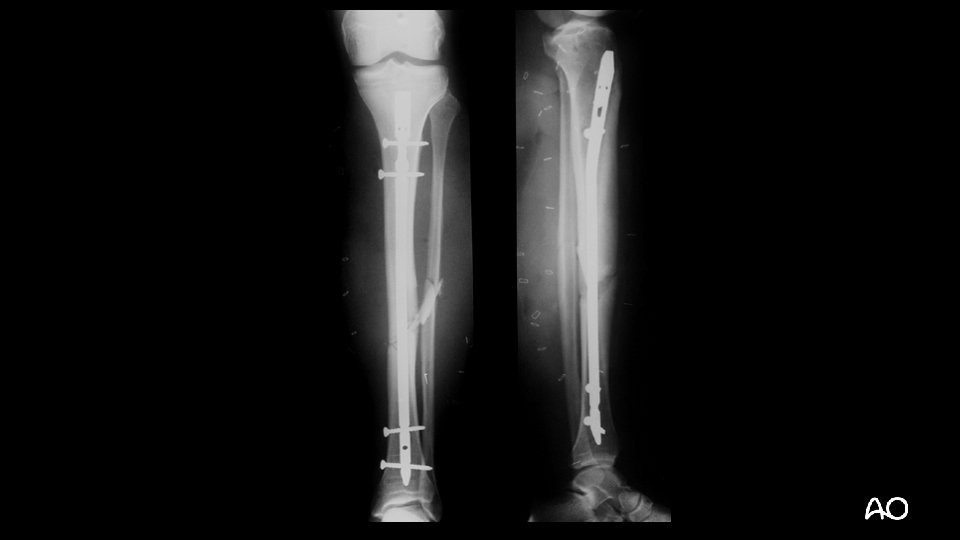

37 -year-old male pedestrian, struck by car bumper • GCS < 8 • ABC stable • No other injuries • Classification:

37 -year-old male pedestrian, struck by car bumper 4 2 A 3 4 F 2 B

4 hours after trauma

37 -year-old male pedestrian, struck by car bumper • 42 A 3, AF 2 B closed fracture • Compartment syndrome

Summary and take-home message • Every injury has two components; a bony injury and a softtissue component. • The soft-tissue injury is just as important as the bony injury. • In complex injuries, it is important to prioritize the individual injuries. • Treatment of the compartment syndrome mandates the stabilization of the bony injury.